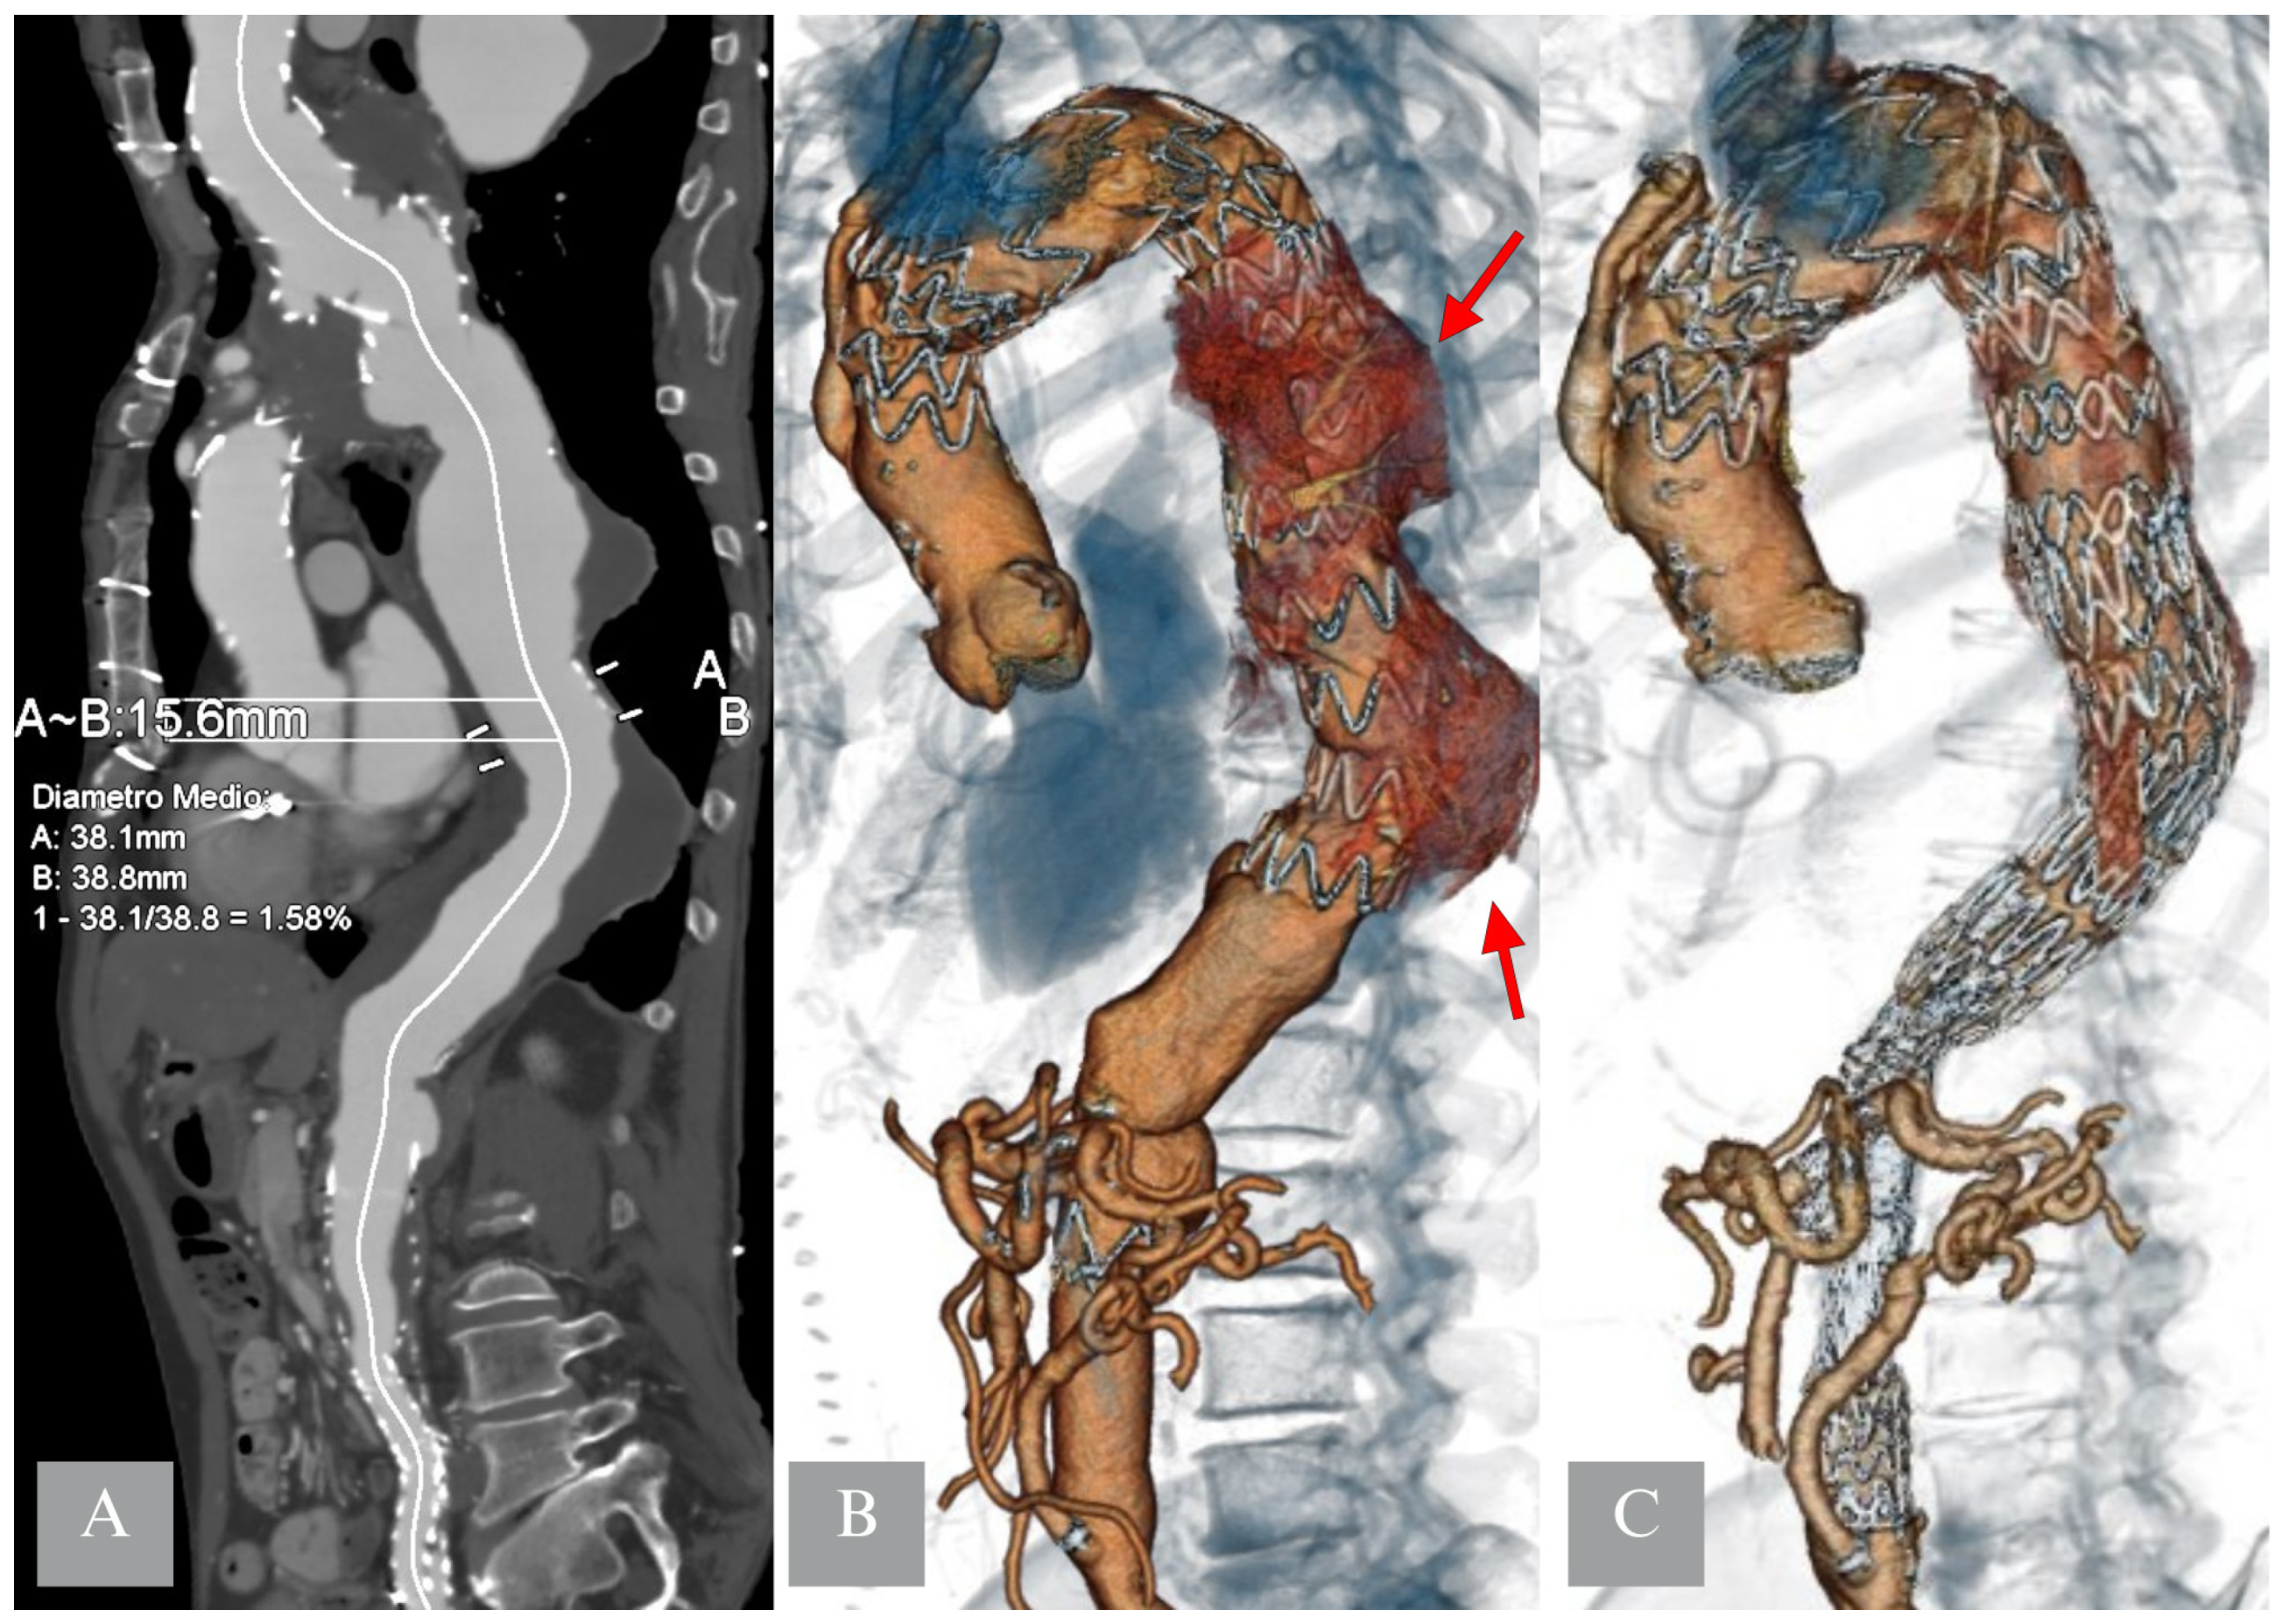

3.1.1. Proximal Thoracic Aortic Repair (PTAR)

- Vivacqua, A.; Idrees, J.J.; Johnston, D.R.; Soltesz, E.G.; Svensson, L.G.; Roselli, E.E. Thoracic endovascular repair first for extensive aortic disease: The staged hybrid approach. Eur. J. Cardio-Thorac. Surg. 2016, 49, 764–769. [Google Scholar] [CrossRef]

- Bertoglio, L.; Katsarou, M.; Loschi, D.; Rinaldi, E.; Mascia, D.; Kahlberg, A.; Lembo, R.; Melissano, G.; Chiesa, R. Elective multistaged endovascular repair of thoraco-abdominal aneurysms with fenestrated and branched endografts to mitigate spinal cord ischemia. Eur. J. Vasc. Endovasc. Surg. 2020, 59, 565–576. [Google Scholar] [CrossRef]